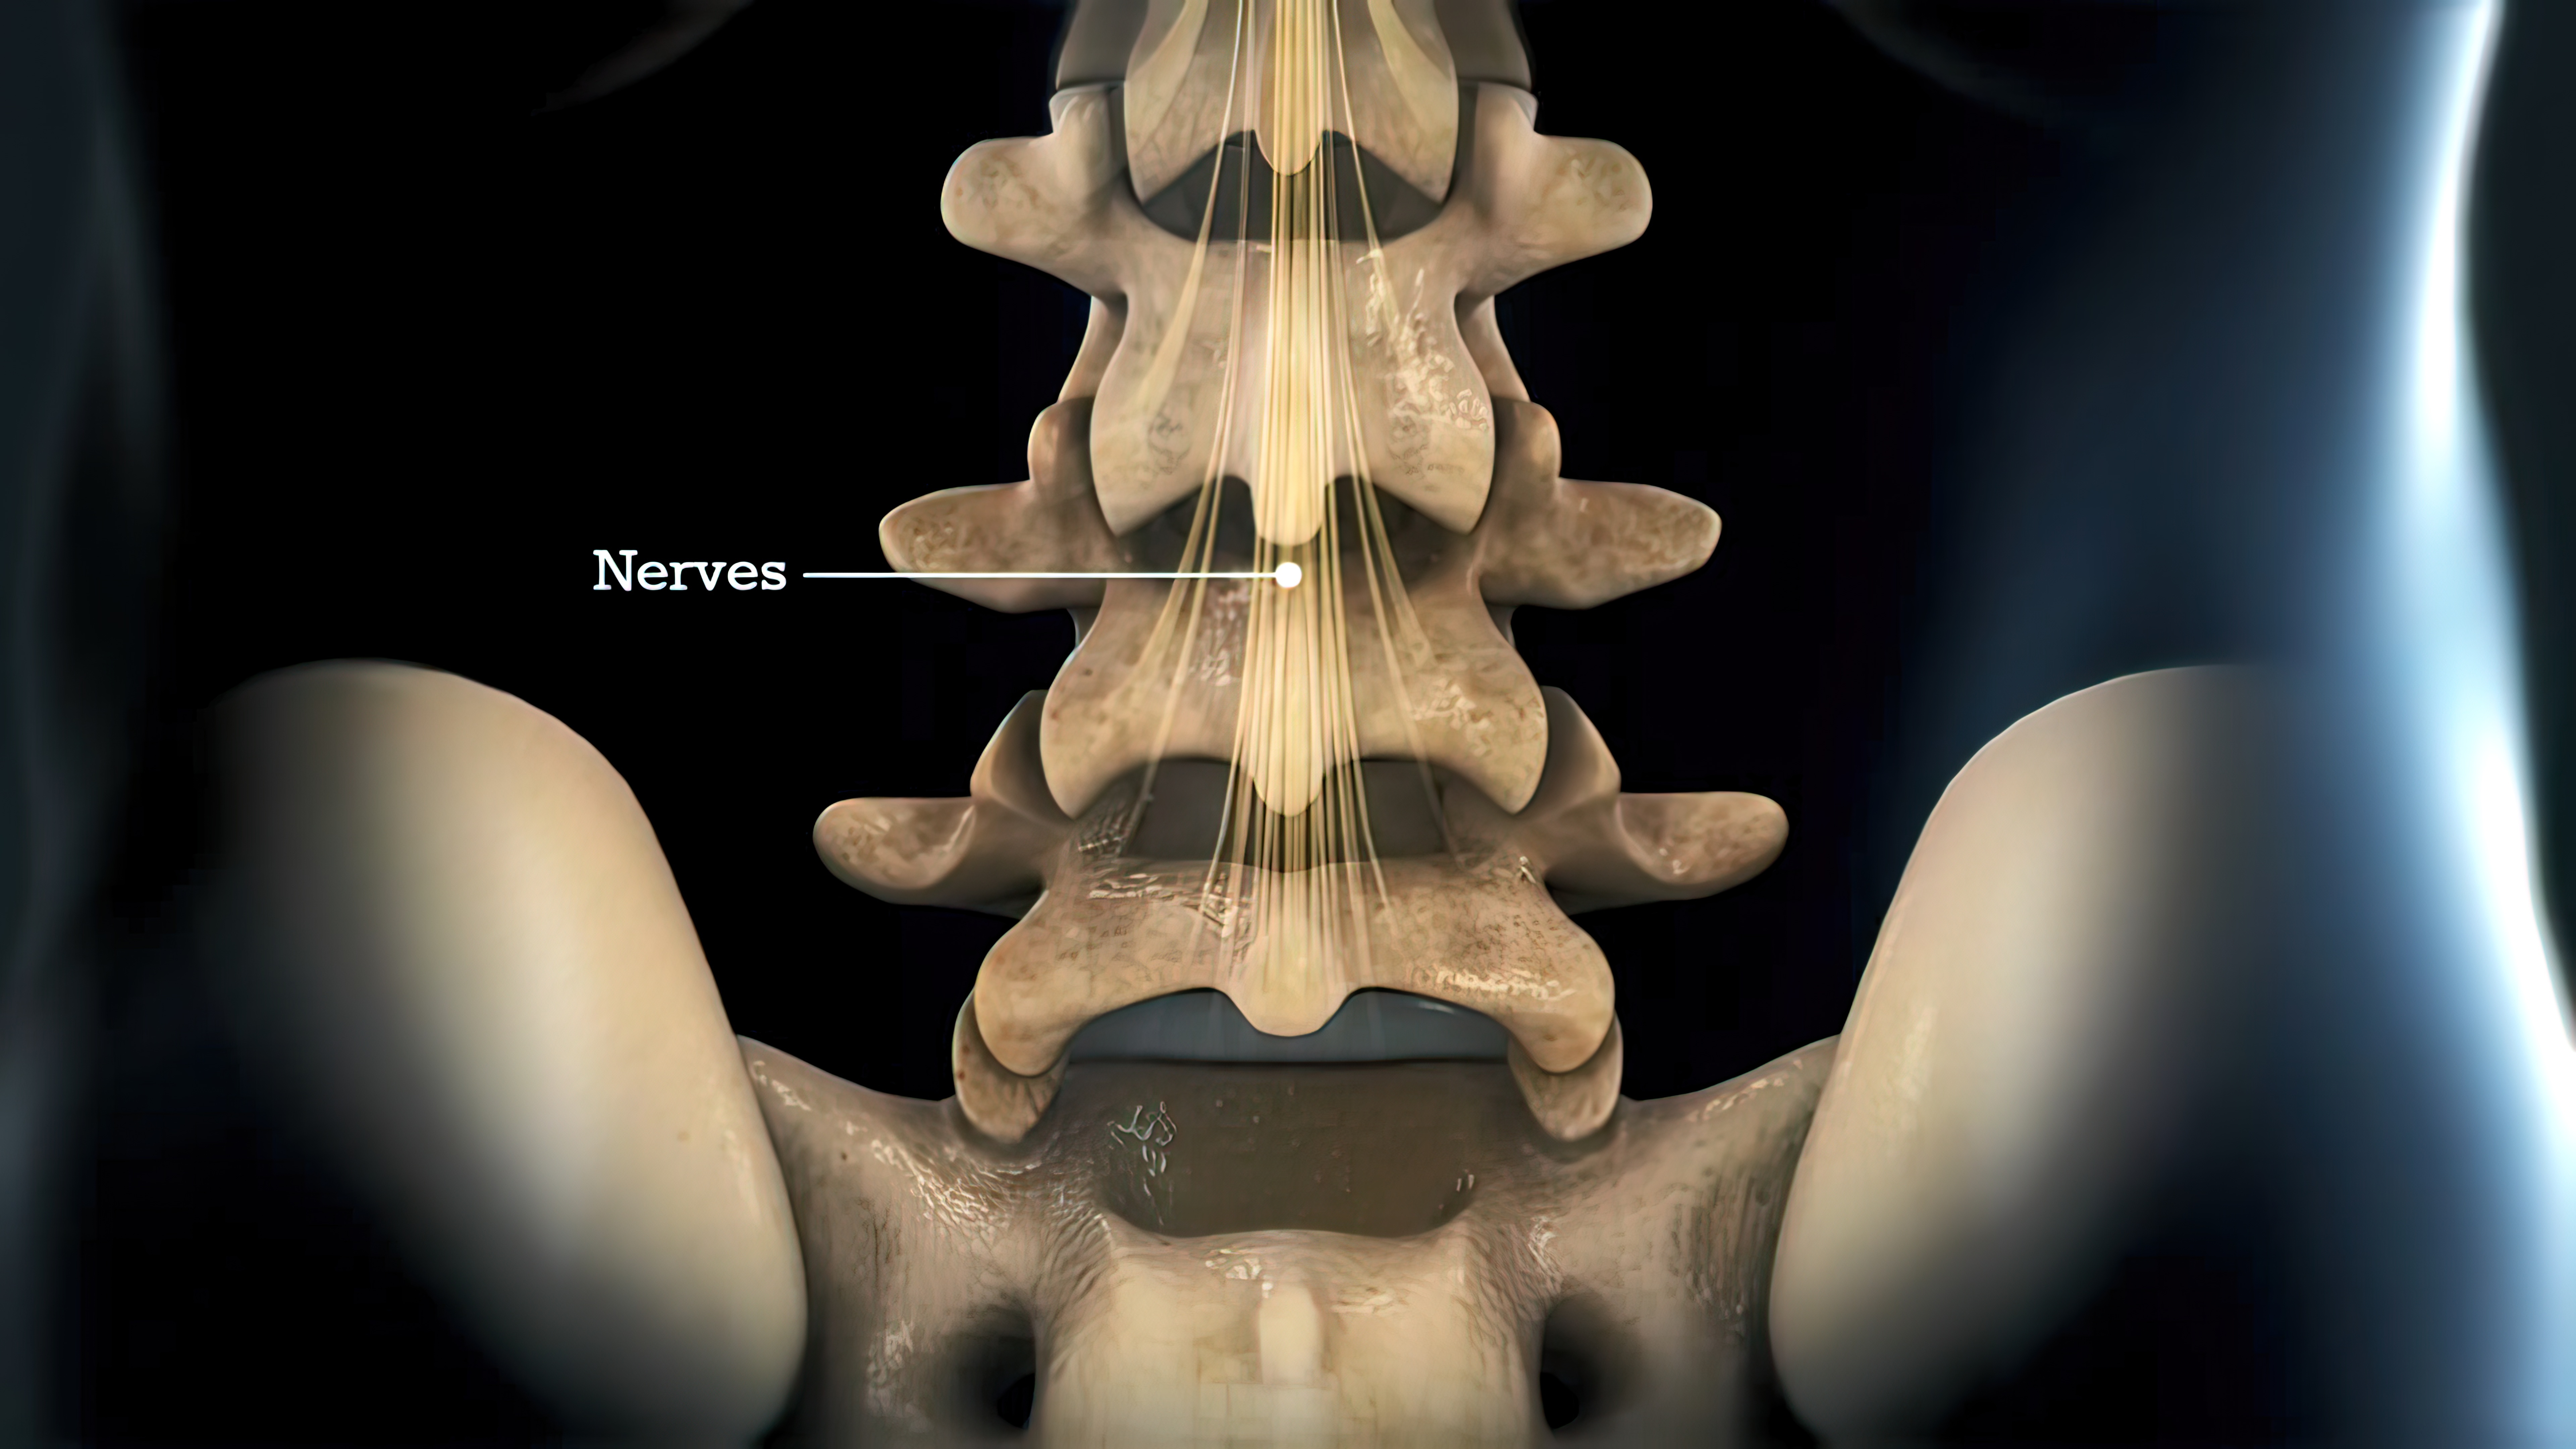

基于MRI的腰椎间盘突出物体积的计算!